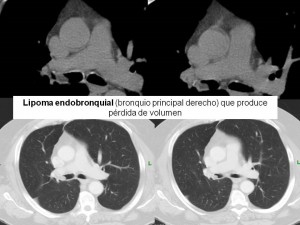

No podemos hacer un diagnóstico final de tumor carcinoide sin haber antes hecho un diagnóstico diferencial con otras posibles patologías, como por ejemplo el hamartoma o el lipoma endobronquial. Este diagnóstico diferencial nos lo dará la broncoscopia.

2. Nódulo endobronquial: Hallazgos derivados de la obstrucción bronquial:

- Oclusión parcial: produce efecto de válvula y consecuentemente atrapamiento aéreo o hiperinsuflación.

- Obstrucción completa: atelectasia o neumonía postobstructiva.